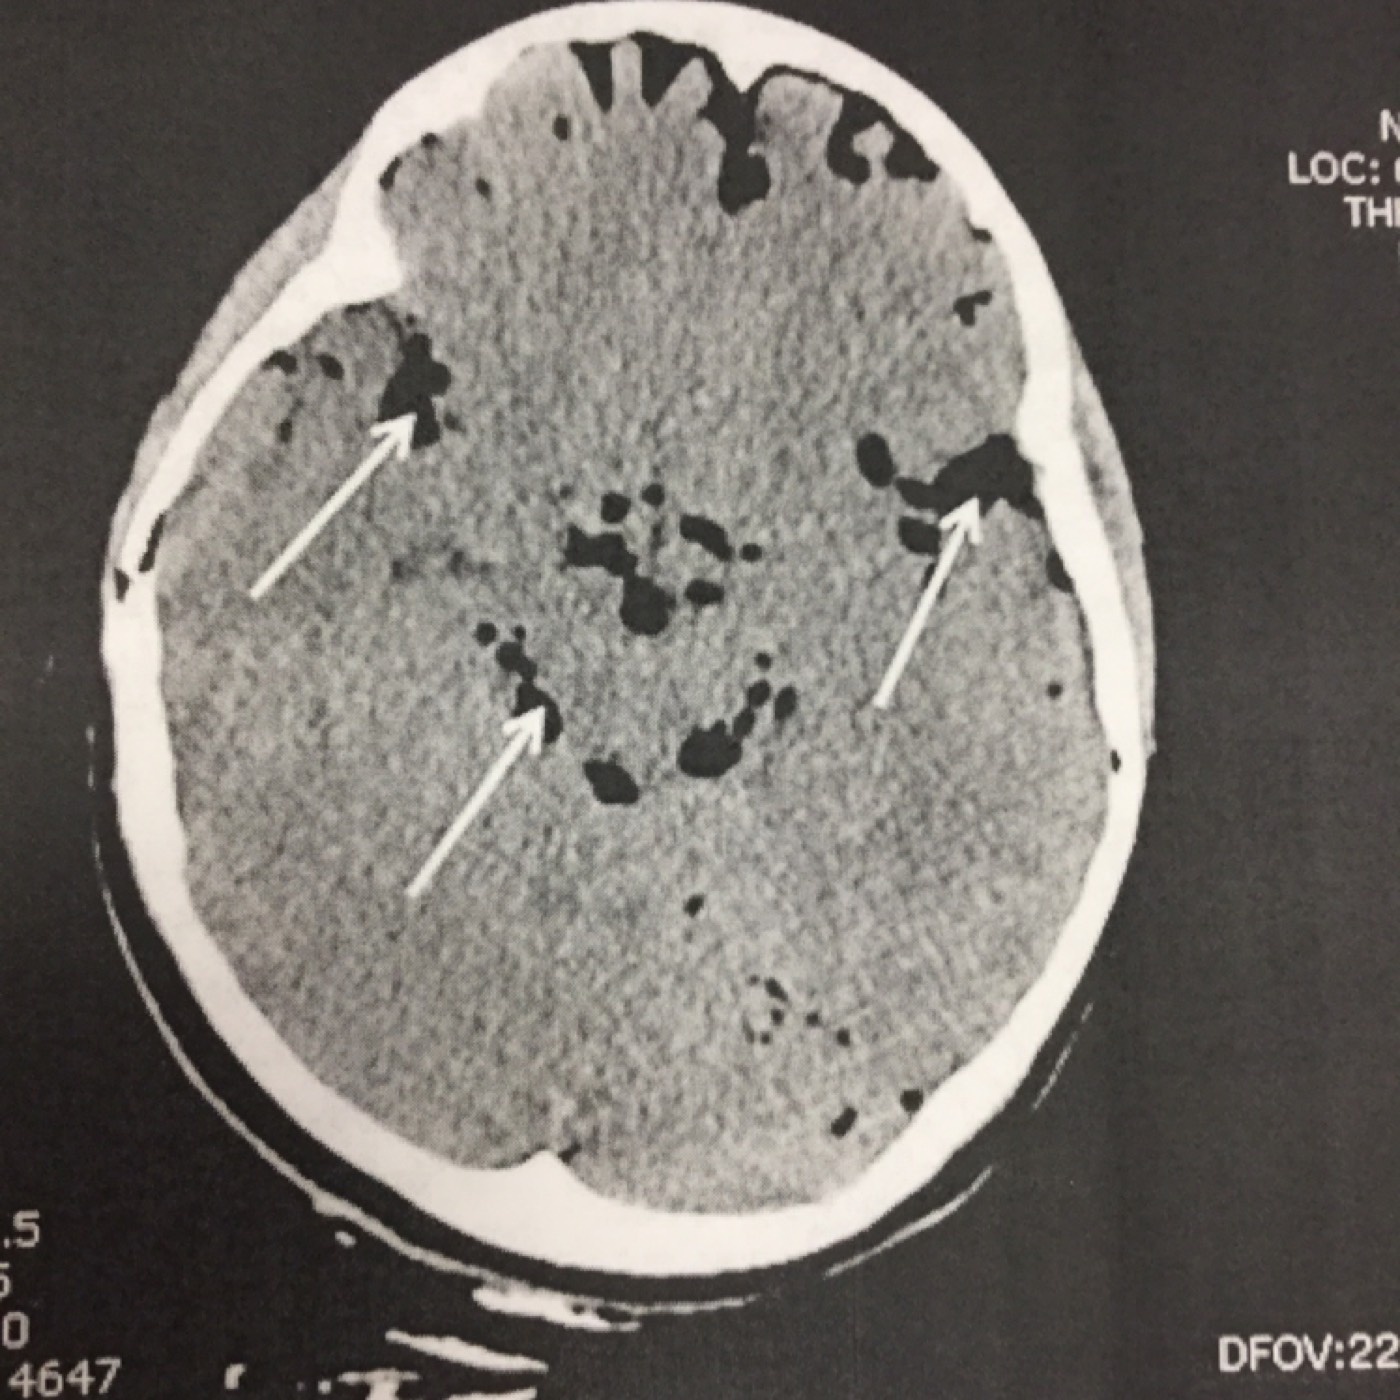

Contributor: Aaron Lessen, MD Educational Pearls: Traumatic Brain Injuries are a frequent complaint in the Emergency Department and have increased in recent years. The American Association for Surgery of Trauma (AAST) has created Brain Injury Guidelines (BIG), in an attempt to categorize brain injuries and the level of treatment they require. They are… BIG 1 Normal neuro exam Not intoxicated Not on anticoagulation or antiplatelet medications Minimal findings on head CT No fracture Maximum of "trace" subarachnoid hemorrhage No intraventricular hemorrhage Monitor for 6 hours No need to repeat the head CT No need to consult neurosurgery BIG 2 Normal neuro exam Not on anticoagulation or antiplatelet medications Any of the following Intoxicated Slightly more findings on head CT Non-displaced skull fracture 4-8 mm bleed (subdural, epidural, intraparenchymal (max two locations)) Maximum of "localized" subarachnoid hemorrhage No intraventricular hemorrhage Hospitalize No need to transfer No need to repeat the head CT No need to consult neurosurgery BIG 3 Abnormal neuro exam On anticoagulation or antiplatelet medications Intoxicated Significant findings on head CT Displaced skull fracture >8 mm bleed (subdural, epidural, intraparenchymal (or more than 2 locations)) "Scattered" subarachnoid hemorrhage Intraventricular hemorrhage Full treatment, admission to trauma center, neurosurgery evaluation References Joseph B, Friese RS, Sadoun M, Aziz H, Kulvatunyou N, Pandit V, Wynne J, Tang A, O'Keeffe T, Rhee P. The BIG (brain injury guidelines) project: defining the management of traumatic brain injury by acute care surgeons. J Trauma Acute Care Surg. 2014 Apr;76(4):965-9. doi: 10.1097/TA.0000000000000161. PMID: 24662858. Joseph B, Obaid O, Dultz L, Black G, Campbell M, Berndtson AE, Costantini T, Kerwin A, Skarupa D, Burruss S, Delgado L, Gomez M, Mederos DR, Winfield R, Cullinane D; AAST BIG Multi-institutional Study Group. Validating the Brain Injury Guidelines: Results of an American Association for the Surgery of Trauma prospective multi-institutional trial. J Trauma Acute Care Surg. 2022 Aug 1;93(2):157-165. doi: 10.1097/TA.0000000000003554. Epub 2022 Mar 28. PMID: 35343931. Summarized by Jeffrey Olson, MS4 | Edited by Jeffrey Olson and Jorge Chalit, OMS4 Donate: https://emergencymedicalminute.org/donate/